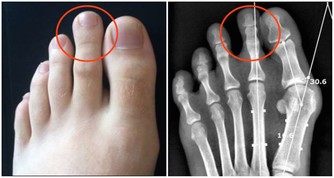

相信大家都不想痛風發作,不僅是因為那滋味太痛苦了,還因為它會帶來各種並發症,比如說關節疼痛,嚴重的甚至會變形,不能正常活動關節。若是尿酸結晶沉積在腎小管裡,還有可能損傷腎臟,形成結石,給身體加上另一重痛苦。